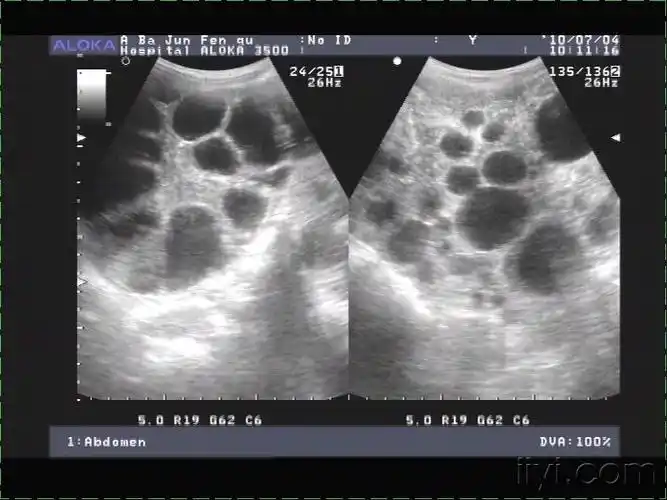

肝包虫病?肝囊性变? - 超声医学讨论版 - 爱爱医医学论坛